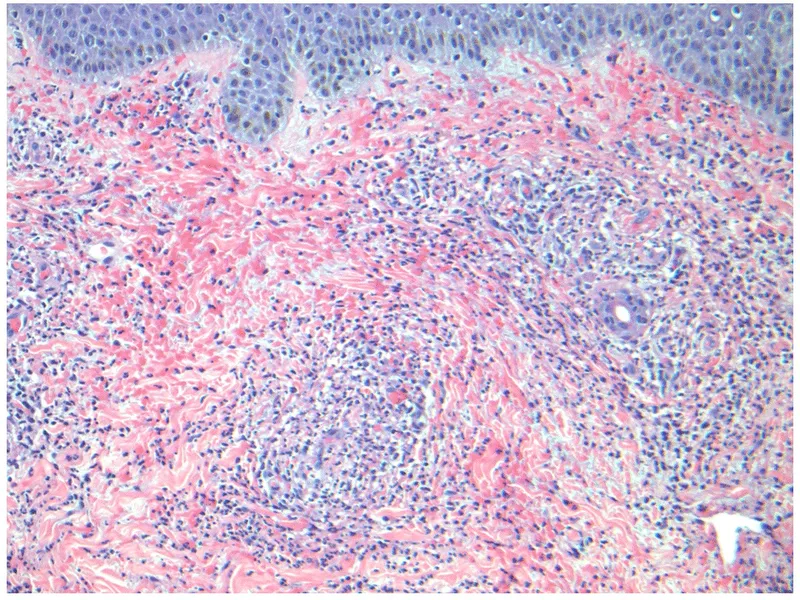

- Biopsy (Gold Standard):

- Site: Skin (newest purpuric lesion for LCV), Kidney (pauci-immune GN in ANCA+), Nerve, Lung.

- DIF: IgA deposition (IgA Vasculitis), C3.

- Palpable purpura: Hallmark of Leukocytoclastic Vasculitis (LCV).